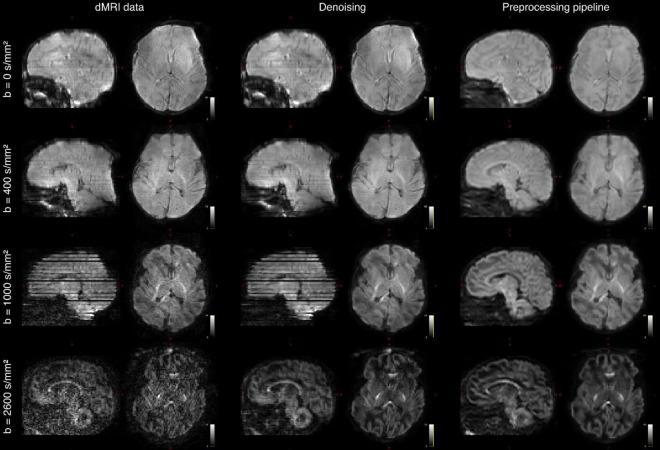

The Developing Human Connectome Project has created a large open science resource which provides researchers with data for investigating typical and atypical brain development across the perinatal period. It has collected 1228 multimodal magnetic resonance imaging (MRI) brain datasets from 1173 fetal and/or neonatal participants, together with collateral demographic, clinical, family, neurocognitive and genomic data from 1173 participants, together with collateral demographic, clinical, family, neurocognitive and genomic data. All subjects were studied and/or soon after birth on a single MRI scanner using specially developed scanning sequences which included novel motion-tolerant imaging methods. Imaging data are complemented by rich demographic, clinical, neurodevelopmental, and genomic information. The project is now releasing a large set of neonatal data; fetal data will be described and released separately. This release includes scans from 783 infants of whom: 583 were healthy infants born at term; as well as preterm infants; and infants at high risk of atypical neurocognitive development. Many infants were imaged more than once to provide longitudinal data, and the total number of datasets being released is 887. We now describe the dHCP image acquisition and processing protocols, summarize the available imaging and collateral data, and provide information on how the data can be accessed.

人类连接组发育项目创建了一个大型开放科学资源,为研究人员提供数据,以调查围产期典型和非典型的大脑发育情况。该项目收集了1173名胎儿和/或新生儿参与者的1228个多模态磁共振成像(MRI)脑部数据集,以及1173名参与者的相关人口统计学、临床、家庭、神经认知和基因组数据。所有受试者在出生时和/或出生后不久,在一台MRI扫描仪上使用专门开发的扫描序列进行研究,这些序列包括新型运动耐受成像方法。成像数据辅以丰富的人口统计学、临床、神经发育和基因组信息。该项目现在正在发布大量新生儿数据;胎儿数据将另行描述和发布。此次发布包括783名婴儿的扫描数据,其中:583名是足月出生的健康婴儿;还有早产儿;以及非典型神经认知发育高危婴儿。许多婴儿接受了多次成像以提供纵向数据,此次发布的数据集总数为887个。我们现在描述dHCP图像采集和处理方案,总结可用的成像和相关数据,并提供有关如何获取这些数据的信息。